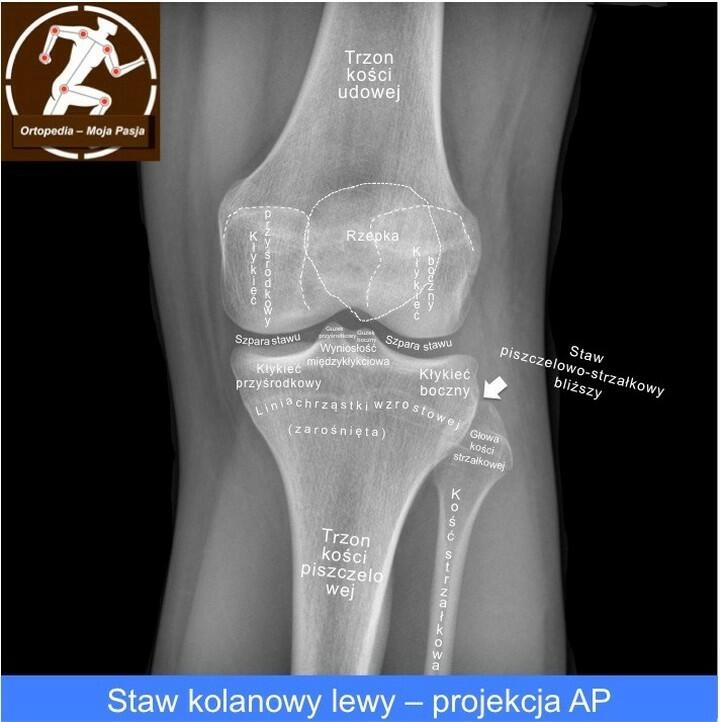

Występująca w stawach chrząstka szklista pokrywa powierzchnię kości wyścielając ją kilkumilimetrową warstwą. Jej obecność umożliwia poruszanie się kości względem siebie, a także amortyzuje wstrząsy.

Niezależnie od tego czy do uszkodzenia chrząstki dochodzi poprzez długotrwałe zbyt duże obciążenia, czy w wyniku jednego silnego urazu ubytek chrząstki powoduje ból, sztywność, ograniczenie ruchomości w stawie i utratę funkcji nogi. Przy całkowitym uszkodzeniu chrząstki elementy kostne nie posiadają amortyzacji, ocierają o siebie co w konsekwencji doprowadza do choroby zwyrodnieniowej stawu. W miejscach styku kości organizm wytwarza osteofity – czyli narośla kostne, co jeszcze bardziej pogłębia ból.